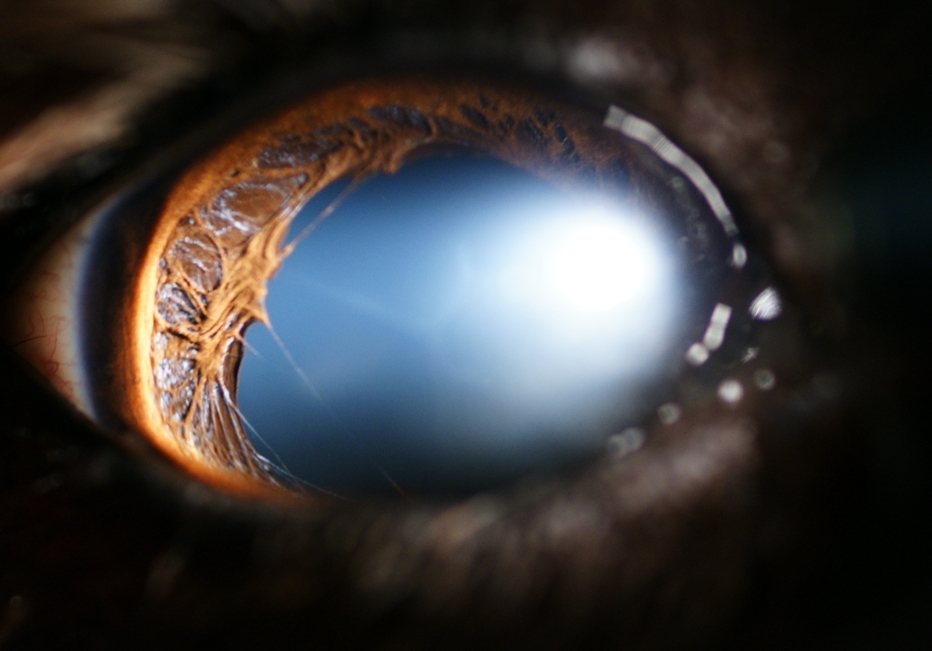

Luxation antérieure du cristallin chez un chien

- 64535 (385.82 Kio) Consulté 2735 fois